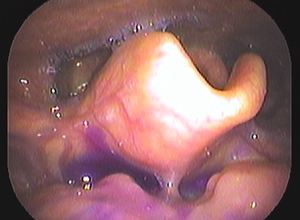

ヒトの鼻はいくつもの空洞に分かれており、それらを副鼻腔といいます(図4)。それぞれの副鼻腔は自然口という小さな通路でつながっていますが、この通路が炎症などでふさがると副鼻腔内で炎症を起こし、粘膜が腫れて粘液がたまります。この状態が長引いたものが慢性副鼻腔炎で、膿がたまると蓄膿症という状態になります。たまった粘液がさらに粘膜の炎症を引き起こし、鼻茸(ポリープ)を増生させることがあります(図5)。ポリープによってにおいの分子が嗅神経に届かないと、嗅覚障害をもたらすことがあります。嗅覚が低下すると味も感じにくくなる味覚障害を自覚することもあります。慢性副鼻腔炎を治すことで、嗅覚障害が改善します。

内視鏡で観察しています。

鼻茸(ポリープ)が確認されています。(黄色*)

主にマクロライド系という抗生物質を使い、飲み薬で炎症を抑える様に治療を開始します。ポリープがある場合には飲み薬での治療は効果があまり期待できません。全身麻酔での手術を勧めています。現在の副鼻腔手術は内視鏡を用い、鼻の穴からすべて手術を行ってしまうので昔のように顔が大きく腫れることはありません。入院は4-7日くらいになりますが、通院可能であれば短縮は可能です。